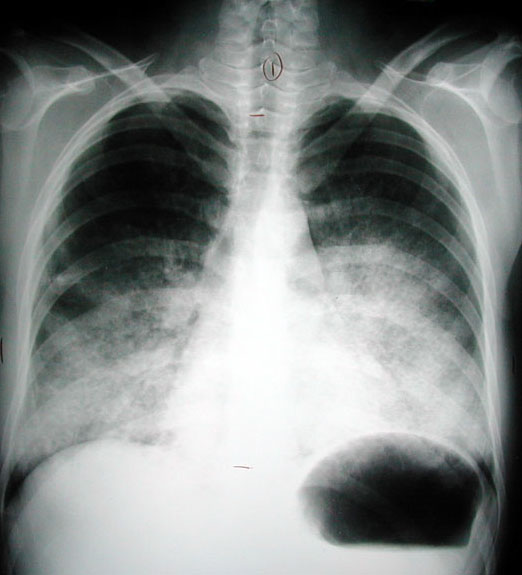

• It is also called "butterfly pattern"

• Note the sparing of lung periphery both in the CT, PA and lateral views

• This is one of the radiologic signs indicative of diffuse alveolar disease

This is an example of alveolar proteinosis.